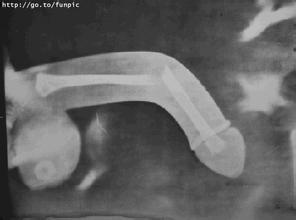

“被切掉的部分差不多有三厘米。”当晚值班的边防医院显微外科主治医生黄志红见到这一幕,也吓了一跳。

据黄医生介绍,这是边防医院第一次接到因“命根子”断裂进行手术的病例。“手术要在显微镜下进行,将一根一根神经血管接回去。”黄医生说,“命根子”上的神经血管是比头发丝还要细好几倍的的物质,只能慢慢地接回去,才能保证血管不被堵塞,正常供血。

此外,手术还需要将被切断的动脉、尿道、海绵体等重新接回去,过程需要非常谨慎。